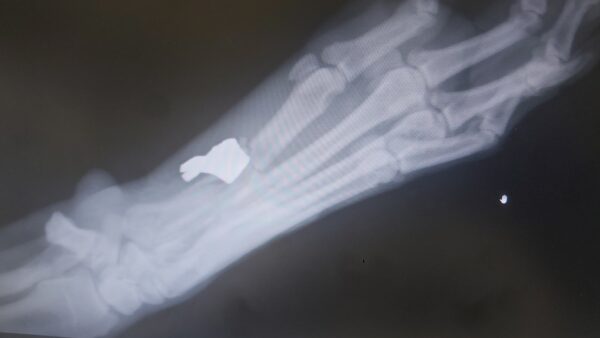

Egy óbudai passzivistánk néhány hónapja megrázó eseményen ment keresztül. Kutyáját, Gizmót az esti sétáltatás közben váratlanul meglőtték. A lábán érte találat. A golyó egy részét kiműtötték, 3 csontja szilánkosra tört, a jobb lábán a főtalppárna nagy része leszakadt, ezt már nem tudták visszavarrni. Az állatorvosi egyetemen még többször megoperálták.

A rehabilitáció a mai napig zajlik, viszont ahhoz, hogy passzivistánk az orvosi kezelést, és a gyógyszereket finanszírozni tudja, ott kellett hagynia lakását és a munkáját, és vissza kellett költöznie szülőfalujába. Nemrég megtalálták Gizmo lábában a golyó másik felét, így vár rá még legalább egy műtét, majd pedig hosszú rehabilitáció.